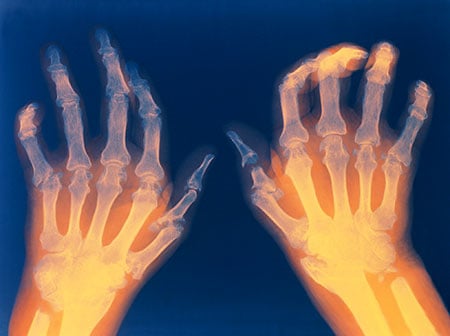

- Joint inflammation helps to distinguish rheumatoid arthritis from common types of arthritis that are not inflammatory, such as osteoarthritis or degenerative arthritis. The distribution of joint inflammation is also important to the doctor in making a diagnosis. In rheumatoid arthritis, the small joints of the hands and fingers, wrists, feet, and knees are typically inflamed in a symmetrical distribution (affecting both sides of the body). When only one or two joints are inflamed, the diagnosis of rheumatoid arthritis becomes more difficult. The doctor may then perform other tests to exclude arthritis due to infection or gout. The detection of rheumatoid nodules (described above), most often around the elbows and fingers, can suggest the diagnosis.

- Joint X-rays may be normal or only show swelling of soft tissues early in the disease. As the disease progresses, X-rays can reveal bony erosions typical of rheumatoid arthritis in the joints. Joint X-rays can also be helpful in monitoring the progression of the disease and joint damage over time. Bone scanning, a procedure using a small amount of a radioactive substance, can also be used to show the inflamed joints. MRI scanning can also be used to show joint damage.

The American College of Rheumatology has developed a system for classifying rheumatoid arthritis that is primarily based upon the X-ray appearance of the joints. This system helps medical professionals classify the severity of your rheumatoid arthritis with respect to cartilage, ligaments, and bone. The system defines the four stages of RA as follows:

Rheumatoid arthritis is a destructive joint disease that is caused by inflammation in the tissue that normally produces lubrication fluid for joints. When this tissue remains inflamed, it leads to deformity by loosening joint ligaments and to joint destruction by eroding away cartilage and bone.

Osteoarthritis is a noninflammatory joint disease whereby the cartilage of the joint thins, typically asymmetrically -- so only one knee or hand may be affected. The illustration on the previous page shows the difference between a normal joint and those of osteoarthritis and rheumatoid arthritis.

In some people with rheumatoid arthritis, chronic inflammation leads to the destruction of the cartilage, bone, and ligaments, causing deformity of the joints. Damage to the joints can occur early in the disease and be progressive. Moreover, studies have shown that the progressive damage to the joints does not necessarily correlate with the degree of pain, stiffness, or swelling present in the joints.